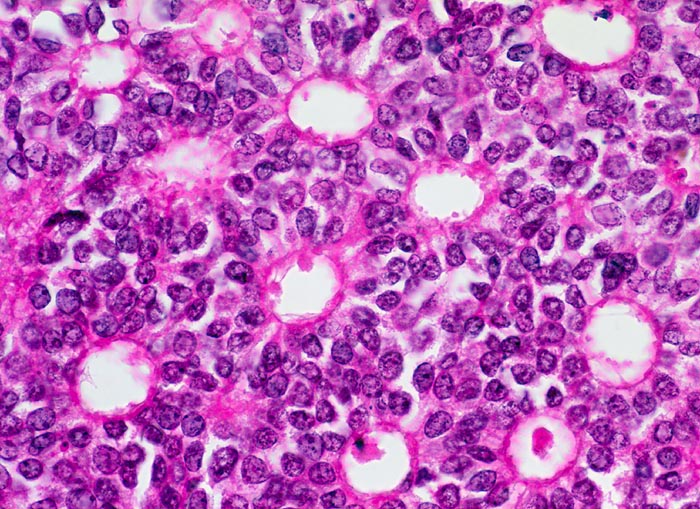

Das duktale Carcinoma in situ (DCIS) wird unterteilt in DCIS mit oder ohne Komedonekrosen. Das DCIS mit Komedonekrosen ist charakterisiert durch offensichtlich maligne Zellen auf nekrotischem Hintergrund. Zytologisch hochdifferenzierte DCIS ohne Komedonekrosen sind monomorpher.

Die individuellen Zellen eines duktalen Carcinoma in situ unterscheiden sich nicht von den Zellen eines invasiven dutkalen Karzinoms. DCIS sind im Gegensatz zum invasiven Karzinom gekennzeichnet durch einen stärkeren Zellzusammenhalt und grössere Uniformität der Verbände mit regelmässigen Abständen der Zellen und geringerem Zellcrowding. Makronukleolen sprechen für ein invasives Karzinom. Kleine Nukleolen hingegen können auch bei benignen Veränderungen auftreten.

Unten werden Beispiele von einem zytologisch hochdifferenzierten und einem zytologsich wenig differenzierten DCIS mit Komedonekrosen gezeigt.